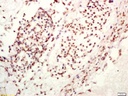

Ten-eleven转运基因1蛋白抗体

目录号:bs-8523R

商品规格:200ul